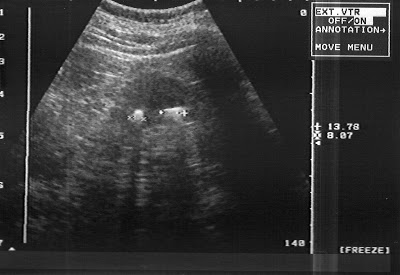

En tercer lugar, nos sirve para determinar el espesor y la ecogenicidad de la corteza o parenquima renal. el espesor normal es de 18 a 20 mm; a medida que la enfermedad renal progresa a estadíos mas avanzados la corteza se va adelgazando, teniendo valores de 10 a 12 mm cuando el riñón ya está en estadíos muy avanzados es decir, cuando ya esta presente una enfermedad renal crónica.

Asimismo, la ecogenicidad de la corteza se altera cuando hay procesos inflamatorios, infecciosos, o inmunológicos, podría definirnos si nos encontramos ante un cuadro agudo o crónico, o ante un rechazo inmunológico en un trasplante, etc.